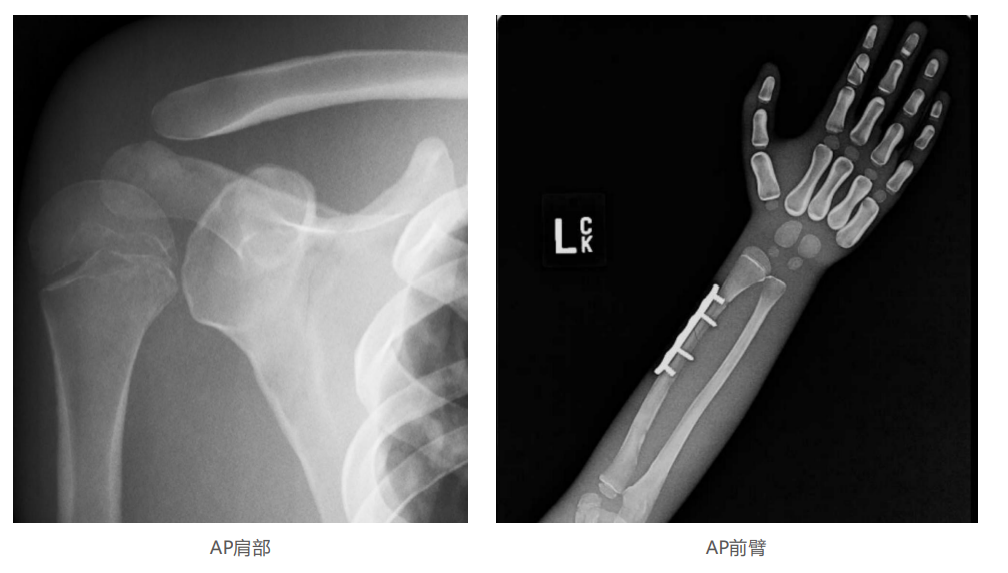

仿真人體模體旨在幫助教學(xué)和提高患者對(duì)體位、準(zhǔn)直和解剖學(xué)的理解,其廣泛的特點(diǎn)有助于安全、高質(zhì)量的人體影像學(xué)的有效指導(dǎo)。

模體的大小和結(jié)構(gòu)都代表了人體模體,使其便攜和易于定位。包括頭、胳膊和腿在內(nèi)的整個(gè)身體。該系列包括六個(gè)部分的模體可單獨(dú)或作為一個(gè)完整的集合。

右肢有伸直或彎曲兩種配置。左臂和左腿可選伴有或不伴有內(nèi)嵌骨折。

骨折版本包含最常見的人體骨折類型 ,包括脛骨扣帶骨折和腓骨普通骨折;

第一跖骨骨折;橈骨切開復(fù)位骨折 ,第二中間趾骨常見骨折。組件由適當(dāng)?shù)木郯滨ズ铜h(huán)氧材料制成,模擬人體組織的X射線衰減特性,用于診斷和治療能量范圍(50 keV - 25 MeV) 。 材料經(jīng)久耐用 ,耐沖擊,適合連續(xù)搬運(yùn)。透明的軟組織有助于解剖標(biāo)志的視覺指示。